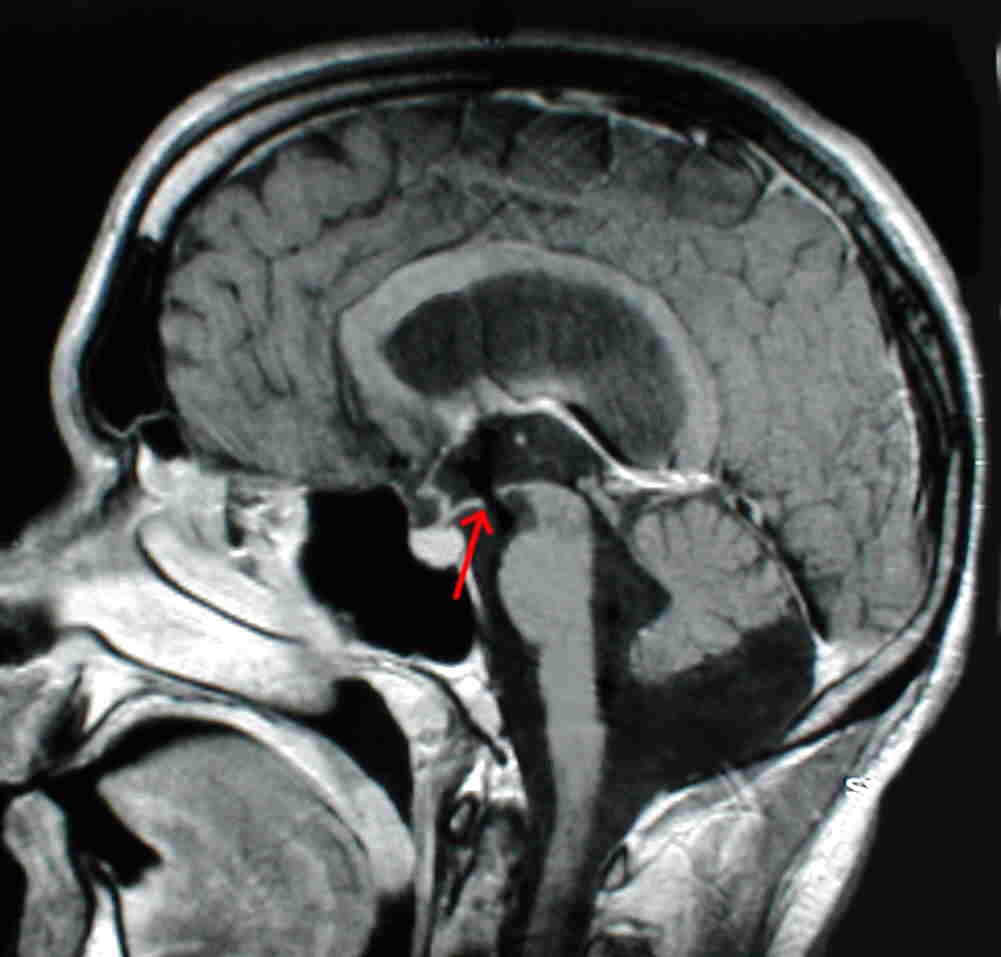

Diese beiden Abbildungen zeigen einen Patienten mit Aquäduktstenose: links vor dem Eingriff und rechts nach endoskopischer Ventrikulozisternostomie. Hierzu wird ein Loch in den Boden des III. Ventrikels gemacht. Der rote Pfeil zeigt die Stelle, wo die Eröffnung des Bodens des III. Ventrikels angelegt wurde. Sehr schon ist zu sehen, dass vermeintlich ein "schwarzer Strich" durch den Boden des III. Ventrikels zieht. Hierbei handelt es sich um schnell fließenden Liquor. Man sieht daran, dass der Liquor wie gedacht die neu geschaffene Umgehung des Aquädukts nutzt, um aus den inneren Hirnwasserkammern in die äußeren Liquorräume zu gelangen. Damit ist das Hindernis, das den Hydrocephalus erzeugte, wirksam umgangen.